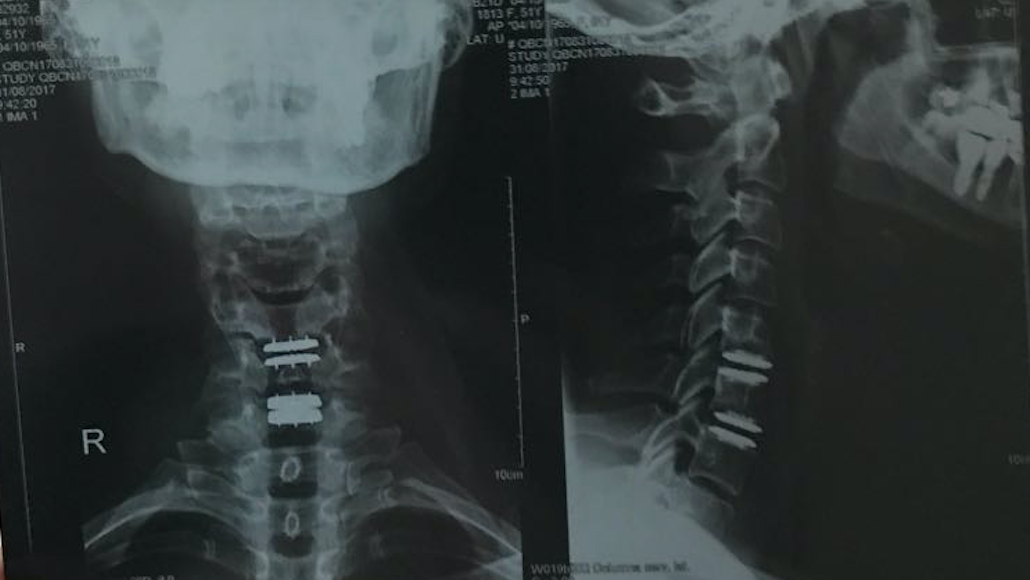

REVERSIÓN DE LA FUSIÓN CERVICAL ANTERIOR MEDIANTE LA COLOCACIÓN DE UNA